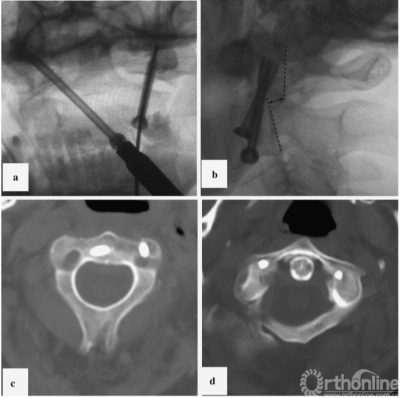

然而,我们尝试复位不成功,无法进行经齿状突融合。因此,我们实施了前路经关节固定技术,左侧螺钉的置入采用Reindl方法。在同一侧,另一颗螺钉采用对侧螺钉路径,并最终置入寰椎右侧侧块(图4)。该病例同样采用空心皮质拉力螺钉(直径4mm;分别使用了22毫米和38毫米的长度)。

图4案例2术后x线影像及CT扫描;a、开口位的x光片;b、侧位x光片,我们继续观察到寰枢关节复合体的背脱位高达4毫米;c、C2椎体螺钉位置;d、螺钉在C1椎体的位置;CT,计算机断层扫描

First, the Halo device attachment was performed for further safe rotation of patient and adequate intraoperative immobilization.We initially planned to perform posterior atlantoaxial fixation; however, the patient exhibited low blood pressure and a decrease in oxygen saturation in the prone position. Considering the high risk of complications, we tried to perform transdental fixation. A standard left-sided submandibular approach was performed, which was complemented by fibrous tissue removal around the fracture. However, our attempts to reduce the dislocation were unsuccessful, therefore, it was impossible to perform the transdental fusion. As a result, the anterior transarticular fixation technique was performed. Insertion of the left screw was performed using the Reindl method. Another screw was inserted into the right lateral mass using a contralateral trajectory through the same approach (Fig.4). Cannulated self-tapping cortical lag screws (4mm in diameter; 22mm and 38mm in length) were used.

Fig. 4 Case 2: post-operative X-ray images and CT scans. a Control X-ray in the transoral plane. b Control X-ray in the lateral plane. We continued to observe dorsal dislocation of the atlantoaxial complex by up to 4 mm. c Screw position in C2 vertebra. d Screw position in C1 vertebra. CT computed tomography